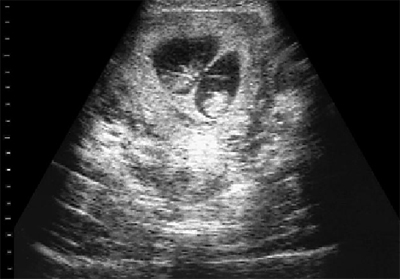

Всього лише кілька десятиліть тому, майбутня мати могла дізнатися про появу на світ одразу двох діток тільки в момент пологів. Сьогодні, коли настав століття, що стрімко розвиваються, нових технологій, за допомогою ультразвукового дослідження, дізнаються про це вже на початкових термінах вагітності. Приблизно починаючи з десятого тижня вагітності, лікар може визначити за допомогою апарату УЗД наявність двох плодів, які розвиваються одночасно.

(3D УЗД двійні)